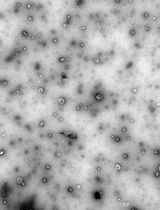

Intravenous hemostats have shown significant promise in prolonging survival for severe noncompressible and internal injuries in preclinical animal models. Existing approaches include the use of liposomes with or without procoagulant enzymes, as well as polymer nanoparticles or soluble biopolymers. While these methods predominantly target or mimic tissue components that are present during coagulation, such as activated platelets and collagen, they may not account for the loss of fibrinogen, which is not only key to clot formation but also the first protein to fall below critical levels in dilutional coagulopathy. This protocol describes the synthesis and in vitro or ex vivo characterization of a crosslinkable nanoparticle system that seeks to address dilutional coagulopathy by leveraging the critical gelation concentration and bioorthogonal click chemistry. The system was shown to only gel at high nanoparticle and crosslinker concentrations, increase the rate of platelet recruitment, and decrease the rate of clot degradation in a low-fibrinogen environment, providing a platform for treating severe hemorrhage in a coagulopathic environment. Ultimately, the contents of this protocol may assist researchers in the in vitro characterization and screening of other crosslinkable nanoparticle systems or hemostats, with potential expansions to other categories of coagulation dysfunction, such as embolism treatment.

• A protocol for the synthesis of nanoparticles with activated-platelet-binding moieties to mimic fibrin.

To this end, we developed a two-component system of dibenzocyclooctyne-functionalized multiarm polymers and nanoparticles with azide and activated-platelet-binding moieties, which leverages the increased accumulation of nanoparticles at the injury [8] to achieve crosslinking above a critical concentration, thereby mimicking the presence of fibrin at the wound site. This platform was demonstrated to result in significantly greater platelet recruitment in both normal and hemodiluted systems, increased resistance to fibrinolysis, and prolonged survival in a mouse liver resection model when compared to targeted nanoparticle-only controls.